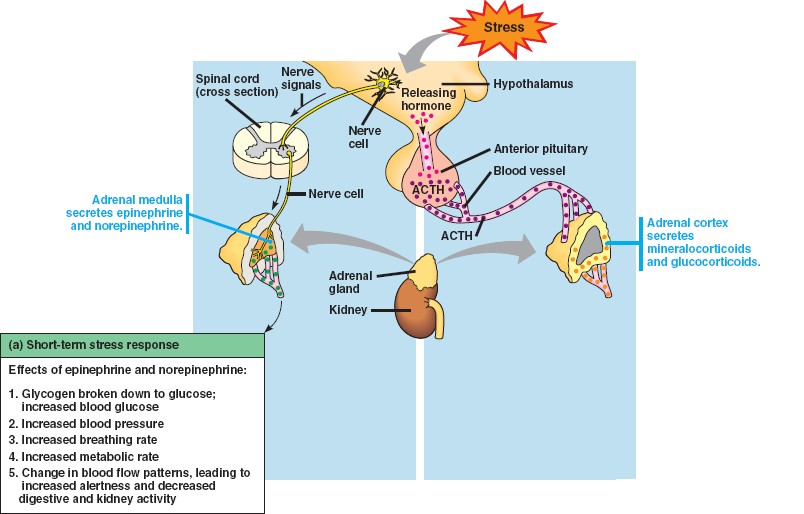

45_13StressAdrenals

45_13StressShort

adrenal_cortex.html

epinephrine.html